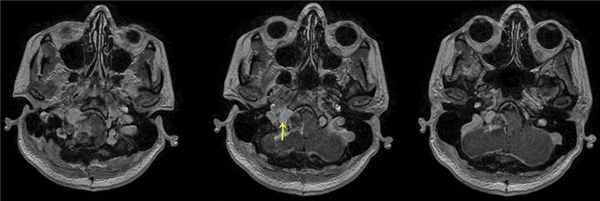

При проведении МРТ головного мозга пациентки В. на 3-и сутки после операции выявлена остаточная часть опухоли в канале подъязычного нерва (рис. 5). Рис. 5. МРТ головного мозга пациентки В. на 3-и сутки после операции. При усилении сигнала парамагнетиком определяется остаток опухоли в канале подъязычного нерва справа (указано стрелкой).